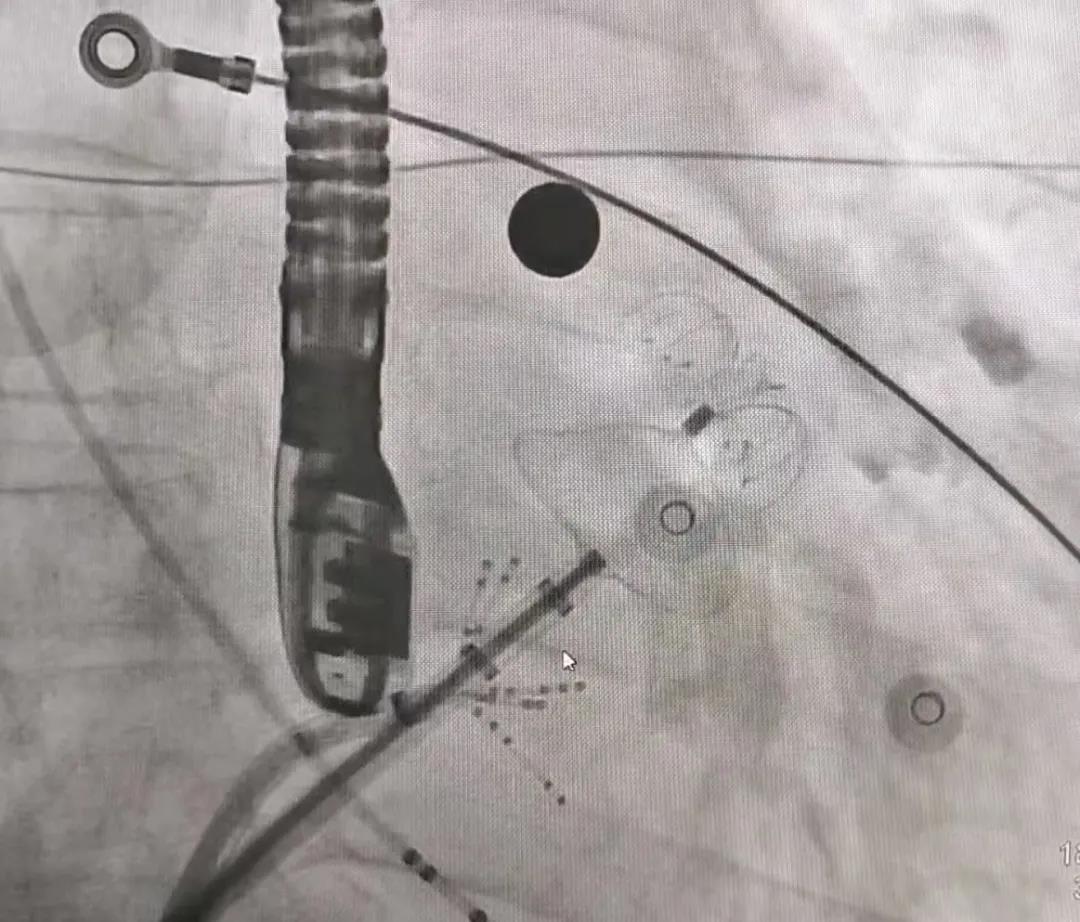

导师面对面:手术演示

武汉亚心医院黄克强医生首先针对三个病例进行了根基情况介绍,让学员参加术前规划造订,随后观摩并参加整个手术过程。随后,苏晞院长携带学员实现了两例鸡翅型左心耳及一例风向标型左心耳的封堵,让参加学员在现实情况中对分歧的左心耳封堵规划进行会商和验证,并切实感触使用LAmbre?左心耳封堵器带来的更佳手术履历。